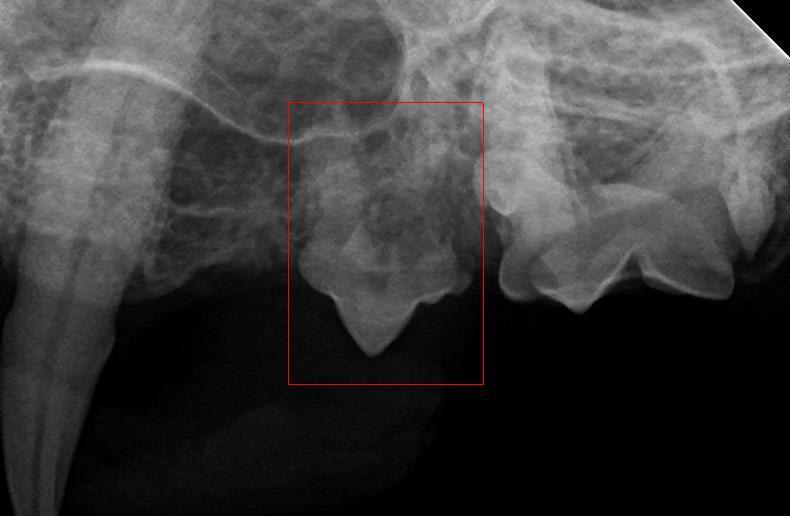

Hello, does this tooth on the picture have resorption? i was told my cat is in pain because of it. please let me know if the tooth has to come out?

Hello and thank you for contacting Petco Pet Education Center, formerly Petcoach. Yes, one of the roots of that premolar tooth shows advanced absorption. It is advisable to extract that tooth as it may produce pain, discomfort or be a source of infection for Yaz.